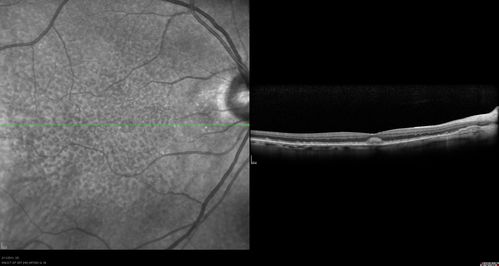

Asymptomatic Juxtapapillary Choroidal Neovascular Membrane - Reticular Macular Disease (Wet AMD)

Asymptomatic Juxtapapillary Bilateral Wet AMD - Reticular Macular Disease - Heidelberg Color Photos